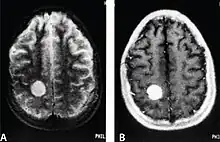

MRI of a cardiac angiosarcoma that has metastasised to the brain.

Primary cardiac angiosarcoma

Primary cardiac angiosarcoma is an angiosarcoma that arises in the heart. Despite being very rare they are the most common malignant primary heart tumor with 10–25%[12][3] of cases being angiosarcomas. Symptoms may include shortness of breath, chest pain (46%[12]), hypotension and syncope. Superior vena cava syndrome is reportedly a complication of cardiac angiosarcoma.[7] Due to the non-specificity of symptoms and rarity of the disease it is often missed by doctors and initial diagnosis may be delayed. A 2012 study reported that 56% of patients presented with pericardial effusion with or without cardiac tamponade.[12] The most common finding on imaging is cardiomegaly. Prognosis is generally very poor with a mean survival rate of three months to four years following diagnosis.[7] Metastasis at time of diagnosis is common.[12]